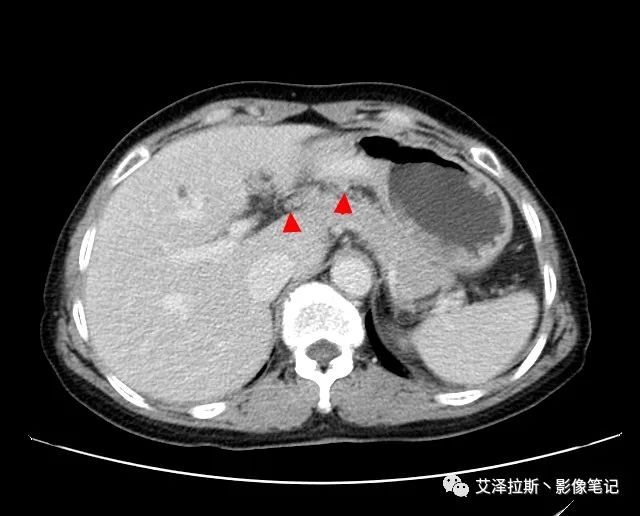

圖2 腫瘤

【影像所見】 胃竇部狹窄,胃壁環(huán)形增厚,小彎側(cè)見一巨大潰瘍,周圍伴“環(huán)堤征”,漿膜面不完整,胃周脂肪見網(wǎng)格狀條索影,病灶與肝臟左葉、胰腺鉤突脂肪間隙消失,增強(qiáng)掃描病灶明顯強(qiáng)化。引流區(qū)內(nèi)約15個區(qū)域淋巴結(jié)受累。

【診斷意見】 胃竇部胃癌(T4N3期) 該病例腫塊突破漿膜層,與肝臟左葉、胰腺鉤突分界不清,脂肪界面消失,定為T4期; 受累及的淋巴結(jié)為15個區(qū)域,定為N3; 有無遠(yuǎn)處轉(zhuǎn)移尚不明確,所以M期暫時無法確定。